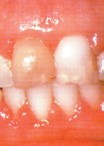

患有牙龈炎,齿龈会红肿,或有出血现象。若刷牙时发觉牙齿容易出血,或牙齿有触痛情况,便需要看牙科医生。

轻度的慢性单纯性牙龈炎所侵犯的是游高龈和龈乳头,严重者可侵犯附着龈、前牙区,尤以下颌前牙炎症明显。咬水果或刷牙时,牙龈出血。健康的牙龈即使用力刷牙,不会发生出血。正常的游离龈是很薄且紧贴牙面,牙龈有炎症时,龈缘充血发红、肿胀、松软,龈缘变厚,牙间乳头变为钝圆,与牙面不紧贴,而且龈沟加深,严重者附着龈可因组织水肿,点彩消失,表面光亮,龈缘可有糜烂或肉芽增生,龈袋溢脓。龈炎进一步发展,牙龈大量毛细血管增生扩张、高度充血,大量炎症细胞和组织液渗出,导致牙龈肥大,可覆盖部分牙冠,此时牙龈呈深红或暗红,探诊极易出血。病程较长者,可导致牙龈纤维增殖,牙龈增生突起,此时牙龈颜色轻度发红或接近正常,质地较硬,出血较少。